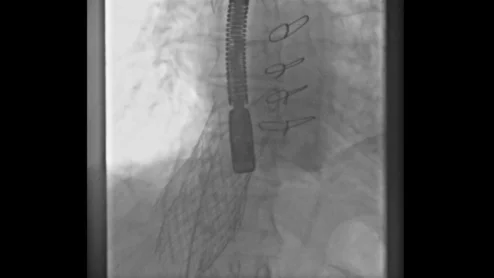

first-in-man valve-in-valve caval valve implantation

A care team in Germany has completed what may be the first structural heart procedure of its kind on a high-risk patient. It started as a straightforward heterotopic caval valve implantation, but then paravalvular leak resulted in a change of plans.